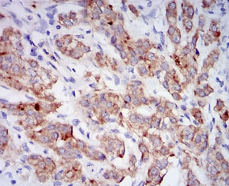

IHC    1/200 - 1/1000